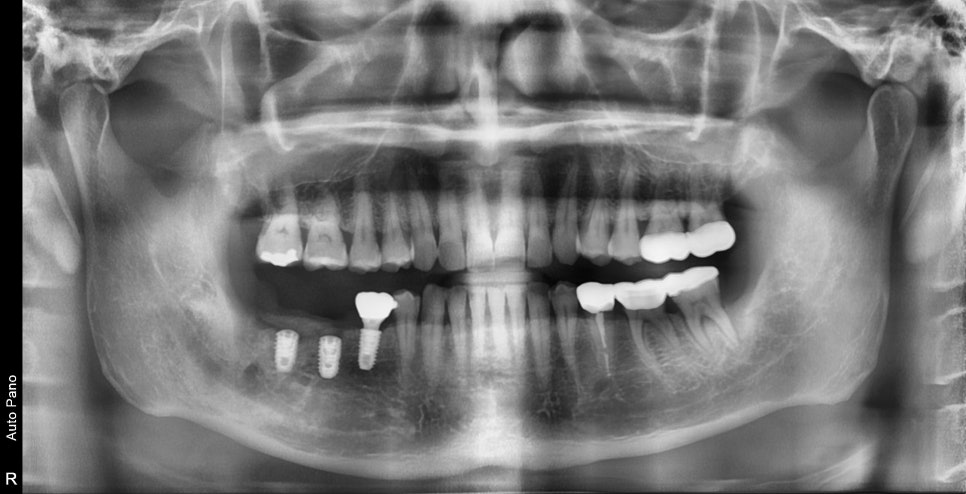

오른쪽 아래 어금니 두개가 흔들리고 부은채로 내원해주셨습니다.

엑스레이상에서 뿌리주변 뼈가 이미 흡수가 되어 동요도가 심한상태로

더이상 치아의 유지는 어려워 보였고 발치 및 임플란트 수술이 필요했습니다.

안타깝게도 자연치아를 살리는것이 어려웠고 발치 진단을 내릴때

후속 치료에 대해 고민할때는 발치 즉시 임플란트 수술이 가능한지가 중요합니다.

바로 수술이 가능할 경우는 전체 치료기간을 2~3달을 줄일수 있기 때문입니다.